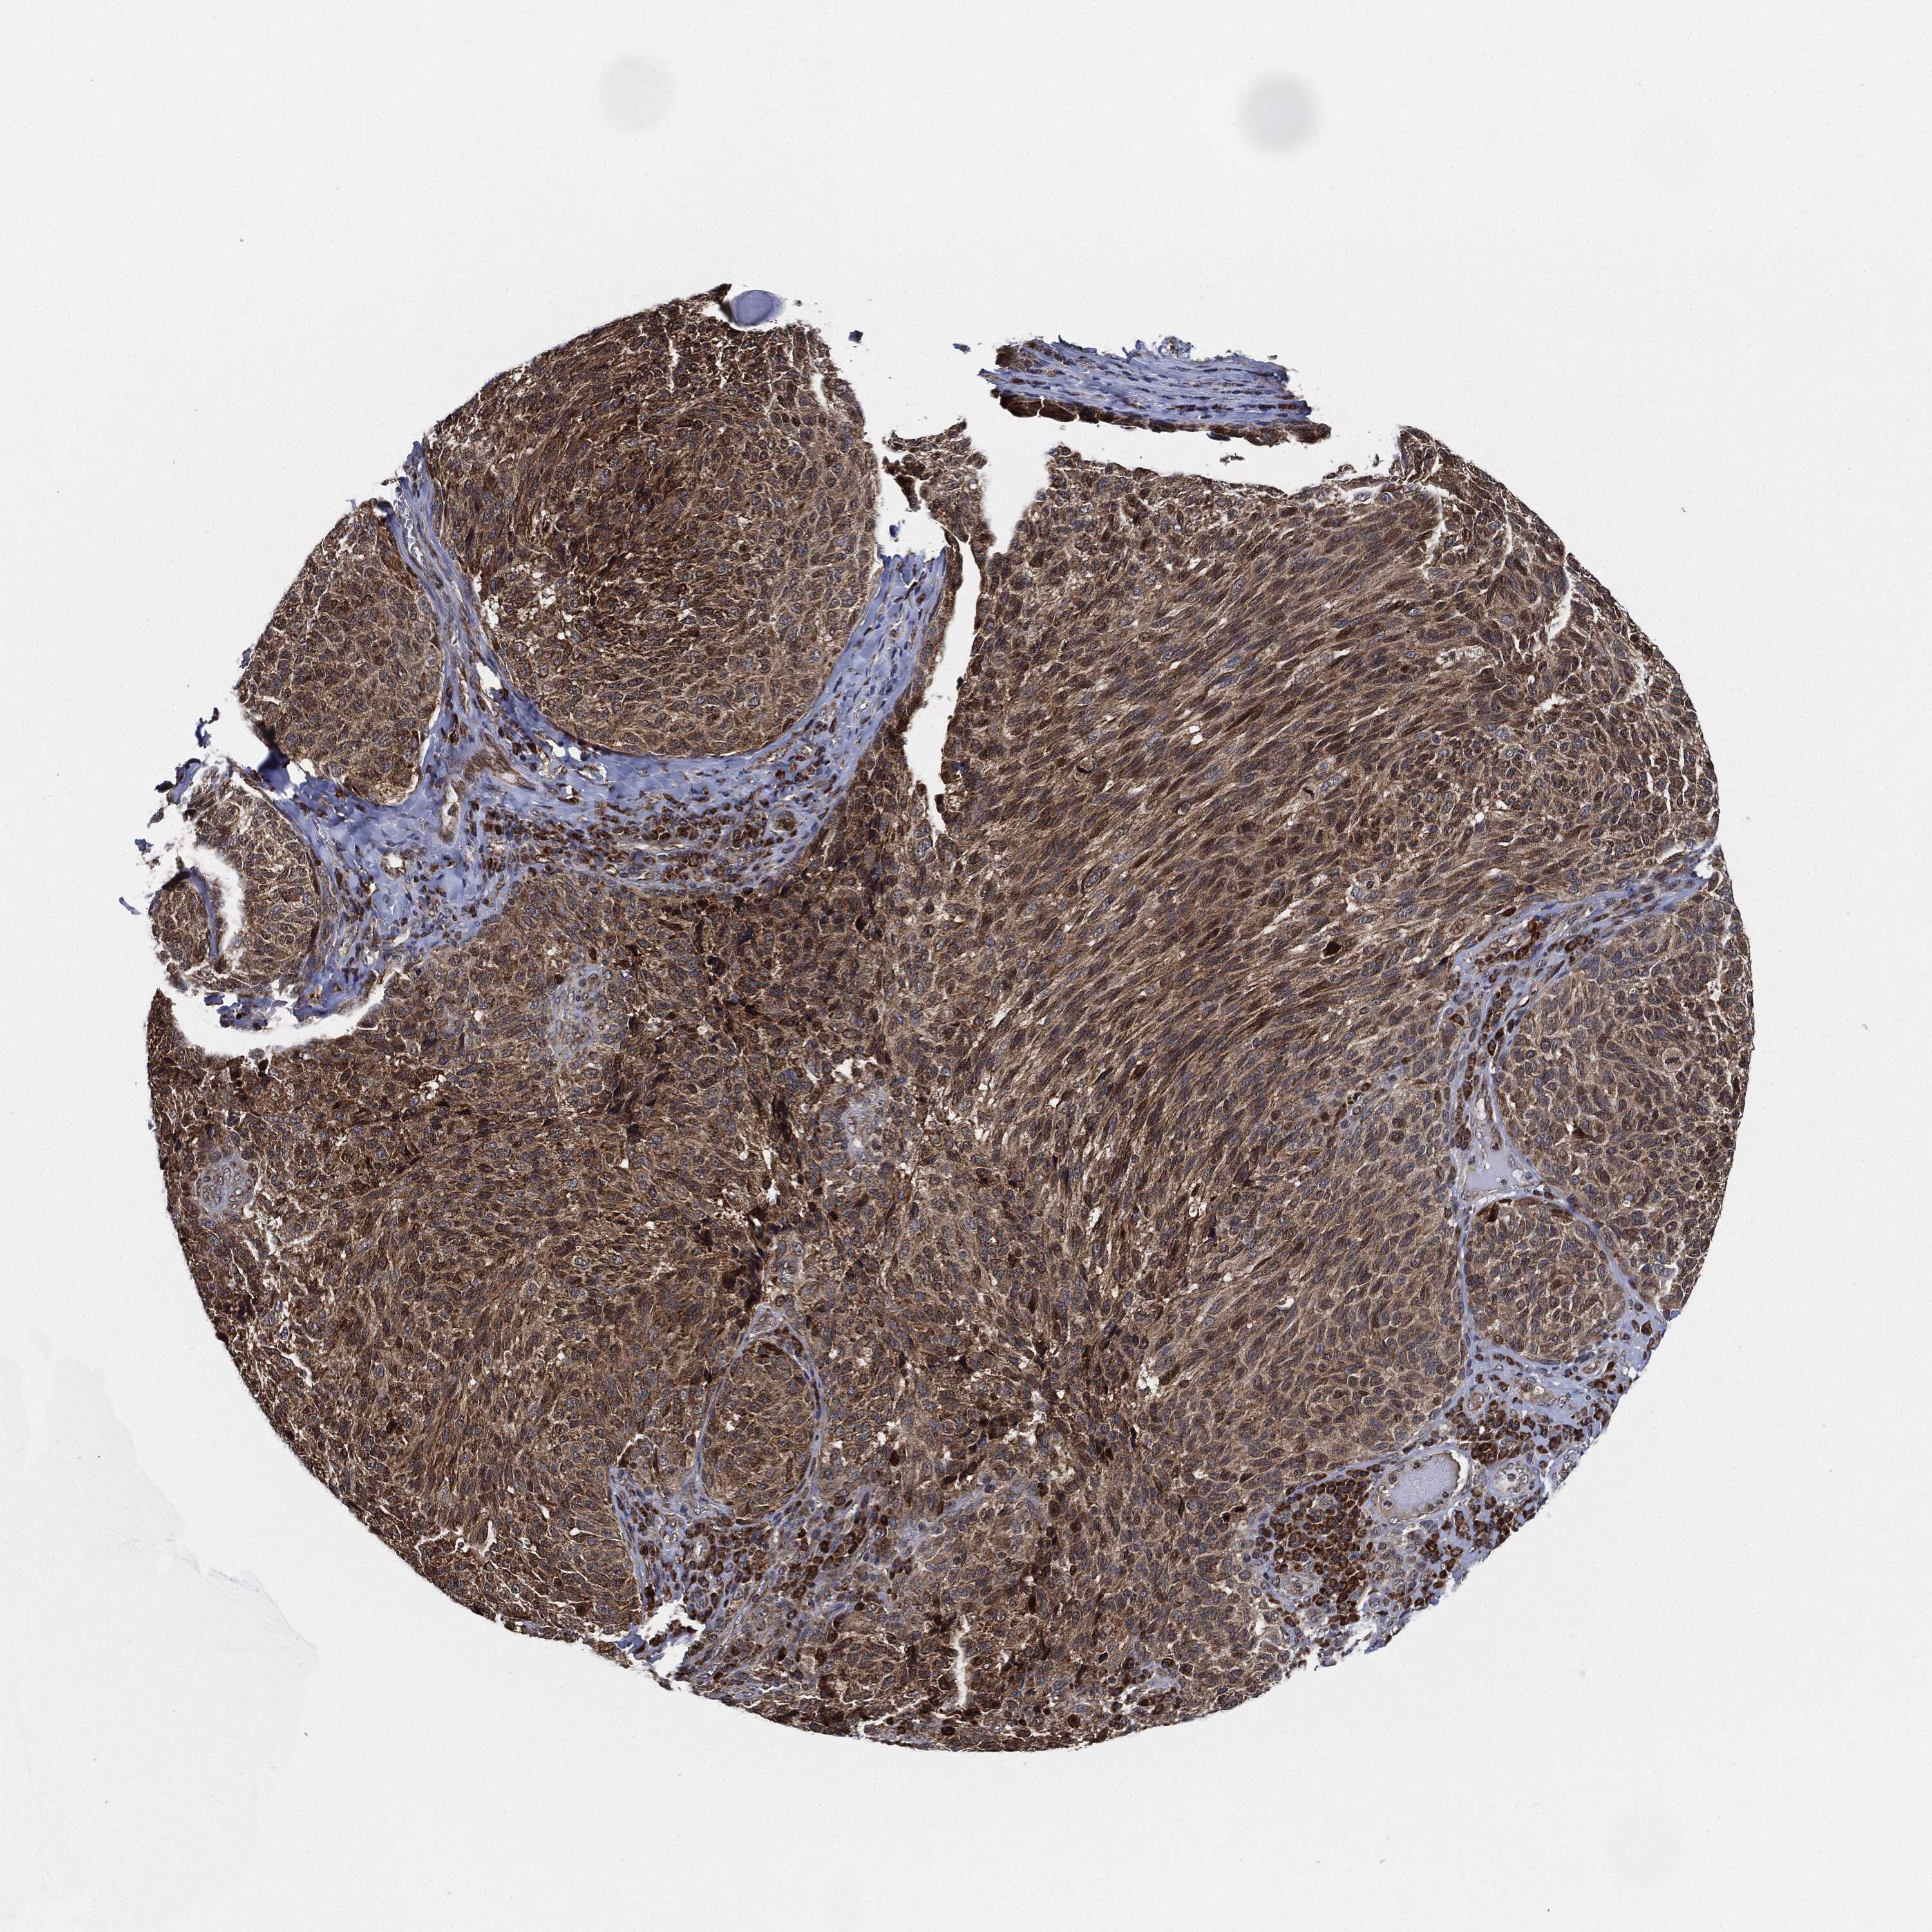

MELANOMA - Protein expressioni

A mouse-over function shows sample information and annotation data. Click on an image to view it in a full screen mode. Samples can be filtered based on level of antibody staining by selecting one or several of the following categories: high, medium, low and not detected. The assay and annotation is described here.

Note that samples used for immunohistochemistry by the Human Protein Atlas do not correspond to samples in the TCGA dataset.

Antibody stainingi

Antibody staining in the annotated cell types in the current human tissue is reported as not detected, low, medium, or high, based on conventional immunohistochemistry profiling in selected tissues. This score is based on the combination of the staining intensity and fraction of stained cells.

Each image is clickable and will lead to virtual microscopy that enables deeper exploration of all samples and also displays staining intensity scores, fraction scores and subcellular localization as well as patient and tissue information for each sample.

Antibody HPA002633

Antibody HPA046758

Antibody CAB010906

Staining

High

Medium

Low

Not detected

Intensity

Strong

Moderate

Weak

Negative

Quantity

>75%

75%-25%

<25%

None

Location

Nuclear

Cytoplasmic/membranous

Cytoplasmic/membranous,nuclear

Malignant melanoma, NOS

Malignant melanoma, Metastatic site

Malignant melanoma in situ